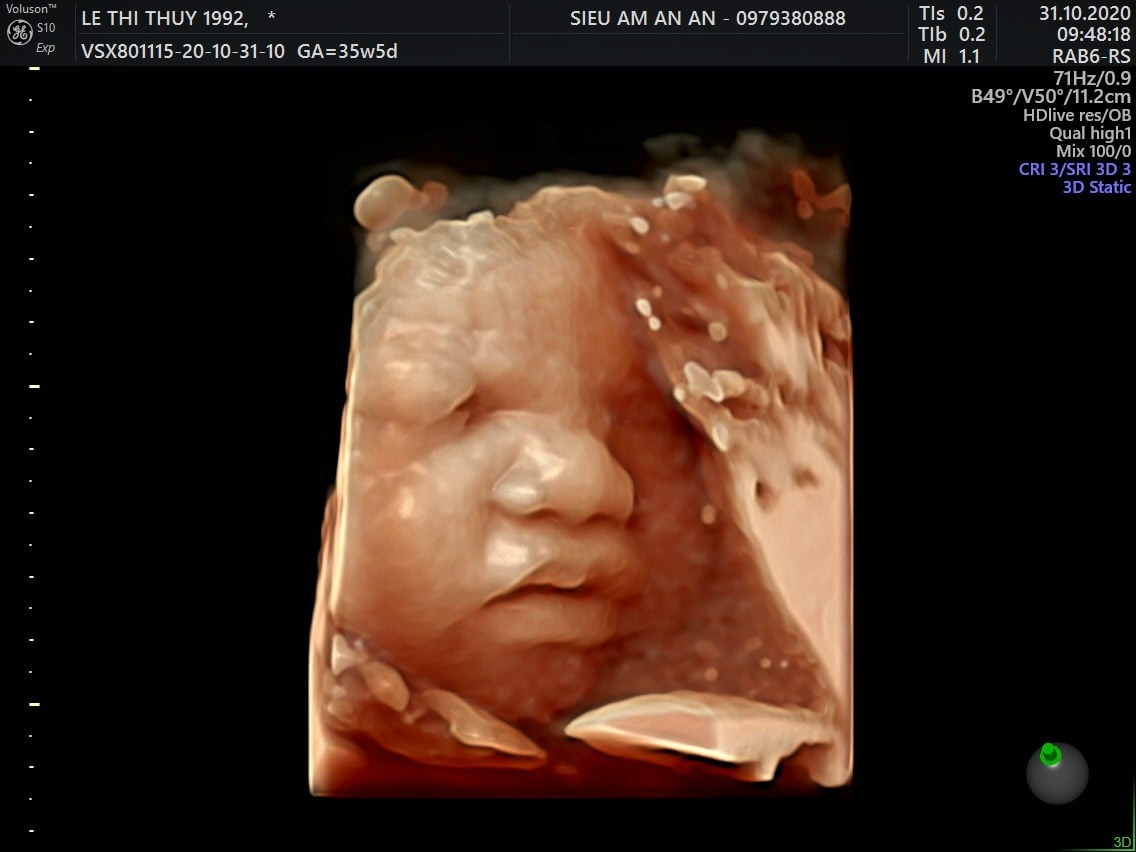

Thai nhi 36 tuần phát triển như thế nào? Ăn gì để con tăng cân, thai 36 tuần gò nhiều, thai 36 tuần nặng bao nhiêu là chuẩn? Qua siêu âm, mẹ có thể thấy hình ảnh một bé yêu mũm mĩm đáng yêu rất giống với em bé sơ sinh hoàn chỉnh. Điều này khiến nhiều mẹ thấy trái tim mình như tan chảy, bé yêu dường như đang đến rất gần rồi.

Chỉ còn khoảng 4 tuần nữa em bé sẽ chào đời, mẹ chắc chắn đang rất tò mò về sự phát triển của bé ở giai đoạn này. Khi mang thai tuần 36, mẹ dễ dàng theo dõi được hình thái của bé qua siêu âm. Các bộ phận chân, tay cử động nhẹ nhàng vô cùng đáng yêu. Hình ảnh mũm mĩm, mập mạp của bé thật sự khiến trái tim mẹ nào cũng phải tan chảy.

Ngược lại, nếu cơn gò nhiều đi kèm các triệu chứng ra máu, vỡ ối, rò rỉ ối, chóng mặt, ngất xỉu, đau liên tục, mẹ cần đến bệnh viện kiểm tra sức khỏe càng sớm càng tốt. Rất có thể mẹ đang đối mặt với hiện tượng sinh non. Qua hình ảnh thai nhi 36 tuần từ máy siêu âm, bác sĩ sẽ đưa ra chỉ định tối ưu nhất.